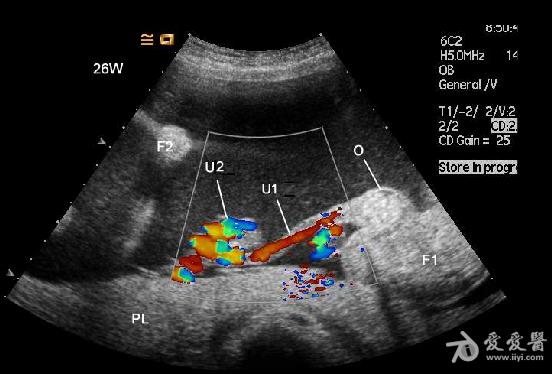

1.CDFI未见异常胎儿心脏显示,但胎体内可见血液流动。

2.无心畸胎的脐带为单脐动脉,PW显示为入胎动脉血流,其血流频谱所显示的心率、心律与正常胎儿的心率、心律完全一致。但其脐动脉的阻力指数明显低于正常胎儿。说明异常胎儿的血供完全来自于正常胎儿心脏的“泵”。

6、频谱及彩色多普勒血流显像可显示无心畸胎脐动脉及脐静脉内血流方向与正常胎儿相反,无心畸胎脐动脉血流从胎盘流向胎儿髂内动脉达胎儿全身,脐静脉血流从胎儿脐部流向胎盘,正好与正常胎儿脐动脉、脐静脉血流方向相反。

1.无心畸胎序列征CDFI可显示胎体内有血液流动,其脐带内有血流信号。而死胎胎体及脐带内无血流显示。